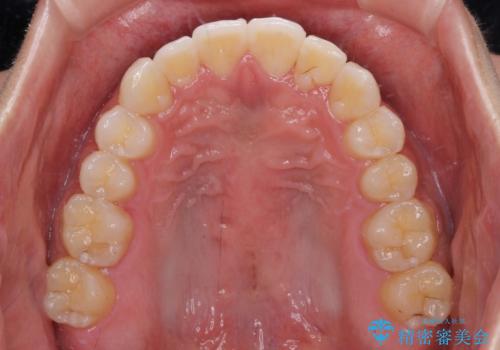

八重歯と奥歯のクロスバイト 上顎骨を拡大してインビザラインで矯正

上顎骨を思い通りに拡大できたため、当初の計画通りに非抜歯矯正で仕上げることができました。